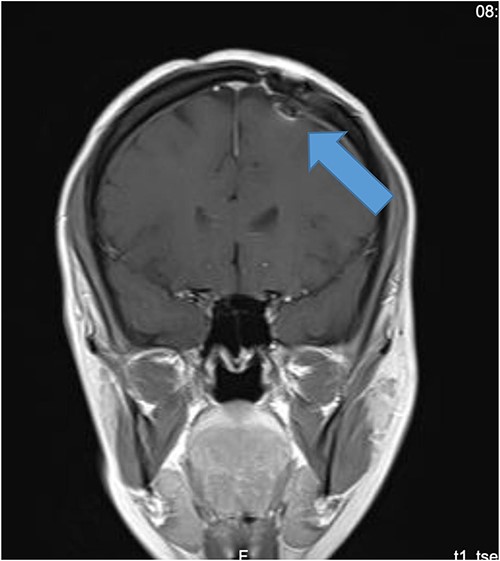

Our patient is a 31-year-old female who presented to the emergency department due to two episodes of generalized tonic colonic seizures. Upon presentation, the patient was administered with supplemental oxygen. She was drowsy and confused while exhibiting signs of right-sided hemiparesis and paralysis. Her pupils were 3 mm and reacted briskly while she showed good left-sided localizing. Her seizures terminated after intravenous administration of midazolam at 5 mg. Further, it was known that she has been symptomatic for 1 month and had been suffering from episodes of seizures, with shaking and tremors of upper limbs, and brief episodes of blackouts for about a minute. These episodes were associated with headache and nausea but were self-limited. Seizures recurred two to three times per week. She denied any fall, tongue bite, loss of consciousness, and limb weakness or numbness. A computerized tomography (CT) scan was suggested, which showed left high parietal hypodensity with vasogenic edema (Fig. 1). She was recommended Keppra 1.5 g and dexamethasone 12 mg. Further, a contrast MRI of the brain was performed (Fig. 2). After a thorough evaluation of the patient’s medical records and current condition, it was decided to proceed with an excision of the tumor using the AC technique. To foster trust and comfort, the same anesthesia and surgical teams were assigned to the patient. Before the procedure, the patient was fully informed about the nature of the procedure and the possibility of a failed outcome or further need for a conversion to general anesthesia. To assess the patient’s cognitive and language abilities, preagreed questions and exercises were performed. These included memory-related queries, such as asking for the patient’s phone number and the names of her dog, and motor commands, such as squeezing a squeaky toy. The patient was prepared for awake navigator-assisted left frontal craniotomy for excision of the left frontal lobe space-occupying lesion, which was suspected to be either a low-grade glioma or fibrous dysplasia. During the surgical procedure, a central line was placed in the right jugular vein using ultrasound, followed by the insertion of a right radial arterial line, a urinary catheter, and two additional venous lines. The patient received a continuous flow of 4–6 l of oxygen per minute. To achieve conscious sedation, the patient received infusions of remifentanil and propofol at varying rates. The patient underwent a 5-hour surgical procedure to remove a tumor. During the procedure, the patient was under sedation and was regularly tested for response to predetermined commands. Her conscious sedation level fluctuated, but she never lost consciousness. The removal of the tumor was successful, and postoperative examination revealed normal motor function and cranial nerve function. The patient was taken to the intensive care unit, and postoperative MRI showed a reduction in the size of the mass lesion in the left frontal lobe/superior frontal gyrus along with mild vasogenic edema surrounding it (Fig. 3).